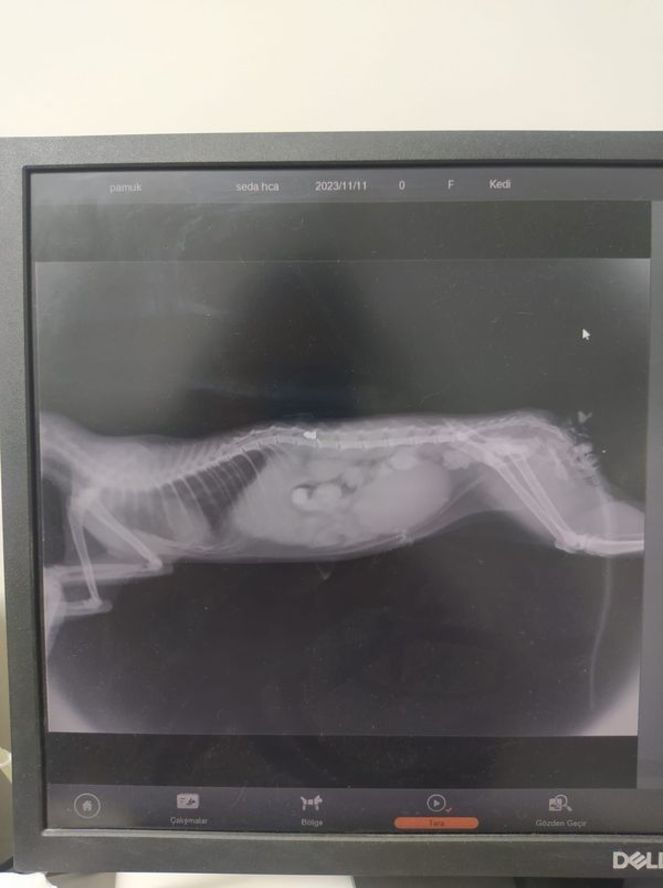

İHA’nın haberine göre, veterinerde çekilen röntgende kedinin kaza yapmadığı omuriliğinde havalı tüfek mermisi bulunduğu ve durumunun kritik olduğu öğrenildi. Ermiş, zaman kaybetmeden yaralı kediyi alarak ameliyat için Adana’da özel bir veteriner kliniğine gitti.

Havalı tüfek mermisinin yürüme sinirlerine zarar verdiğini söyleyen veteriner hekim İsmail Serdar Sayar, “Osmaniye’den geldi belinden saçmayla vurulmuş ve L1 omurga dediğimiz omura saçma saplanmış. Ameliyatında şunu gördük o saçma kemiği kırıyor ve içeri giriyor. Spiral kont dediğimiz omurilik sinirinin üzerine yapışıyor. Biz usulüne uygun bir şekilde çıkardık, ancak ciddi anlamda hasar vardı. Omuriliğinde gerekli işlemler yapıldı. Şu anda genel durumu iyi ama yürüyüp yürümemesi biraz şansına kalmış durumda. Çünkü siniri bizim onarma, yenileme şansımız yok. Umarım iyi bir netice olur. Çok sevimli masum bir arkadaş” ifadelerini kullandı.

“Sokakta arka ayaklarını kullanamaz vaziyette bir kedi bulduk daha sonra Osmaniye’de bir veteriner kliniğine götürdük. Biz en başta bir araba kazası diye düşünmüştük. Ancak röntgen sonrası omurgasında saçma olduğunu gördük. Bu işin ciddi bir durum olduğunu bildiğimiz için ve ameliyat olması gerektiği o saçmanın vücuttan omurgadan uzaklaştırılması gerektiği için Adana’ya geldik. Ameliyatı başarılı bir şekilde gerçekleştirildi. Biraz daha zaman geçsin kendini toparladıktan sonra fizik tedaviye başlayabileceğiz. Doktor ameliyat sonrası, hayvanın hedef alınarak havalı tüfekle vurulduğunu söyledi. Bu bizi elbette daha fazla üzdü. Bu tarz bir olayın yaşanmış olması gerçekten çok üzücü. Herkes hayvanlarla ilgilenemeyebilir ama en azından zarar verilmezse bu bizim için büyük bir kazanç olacak.”